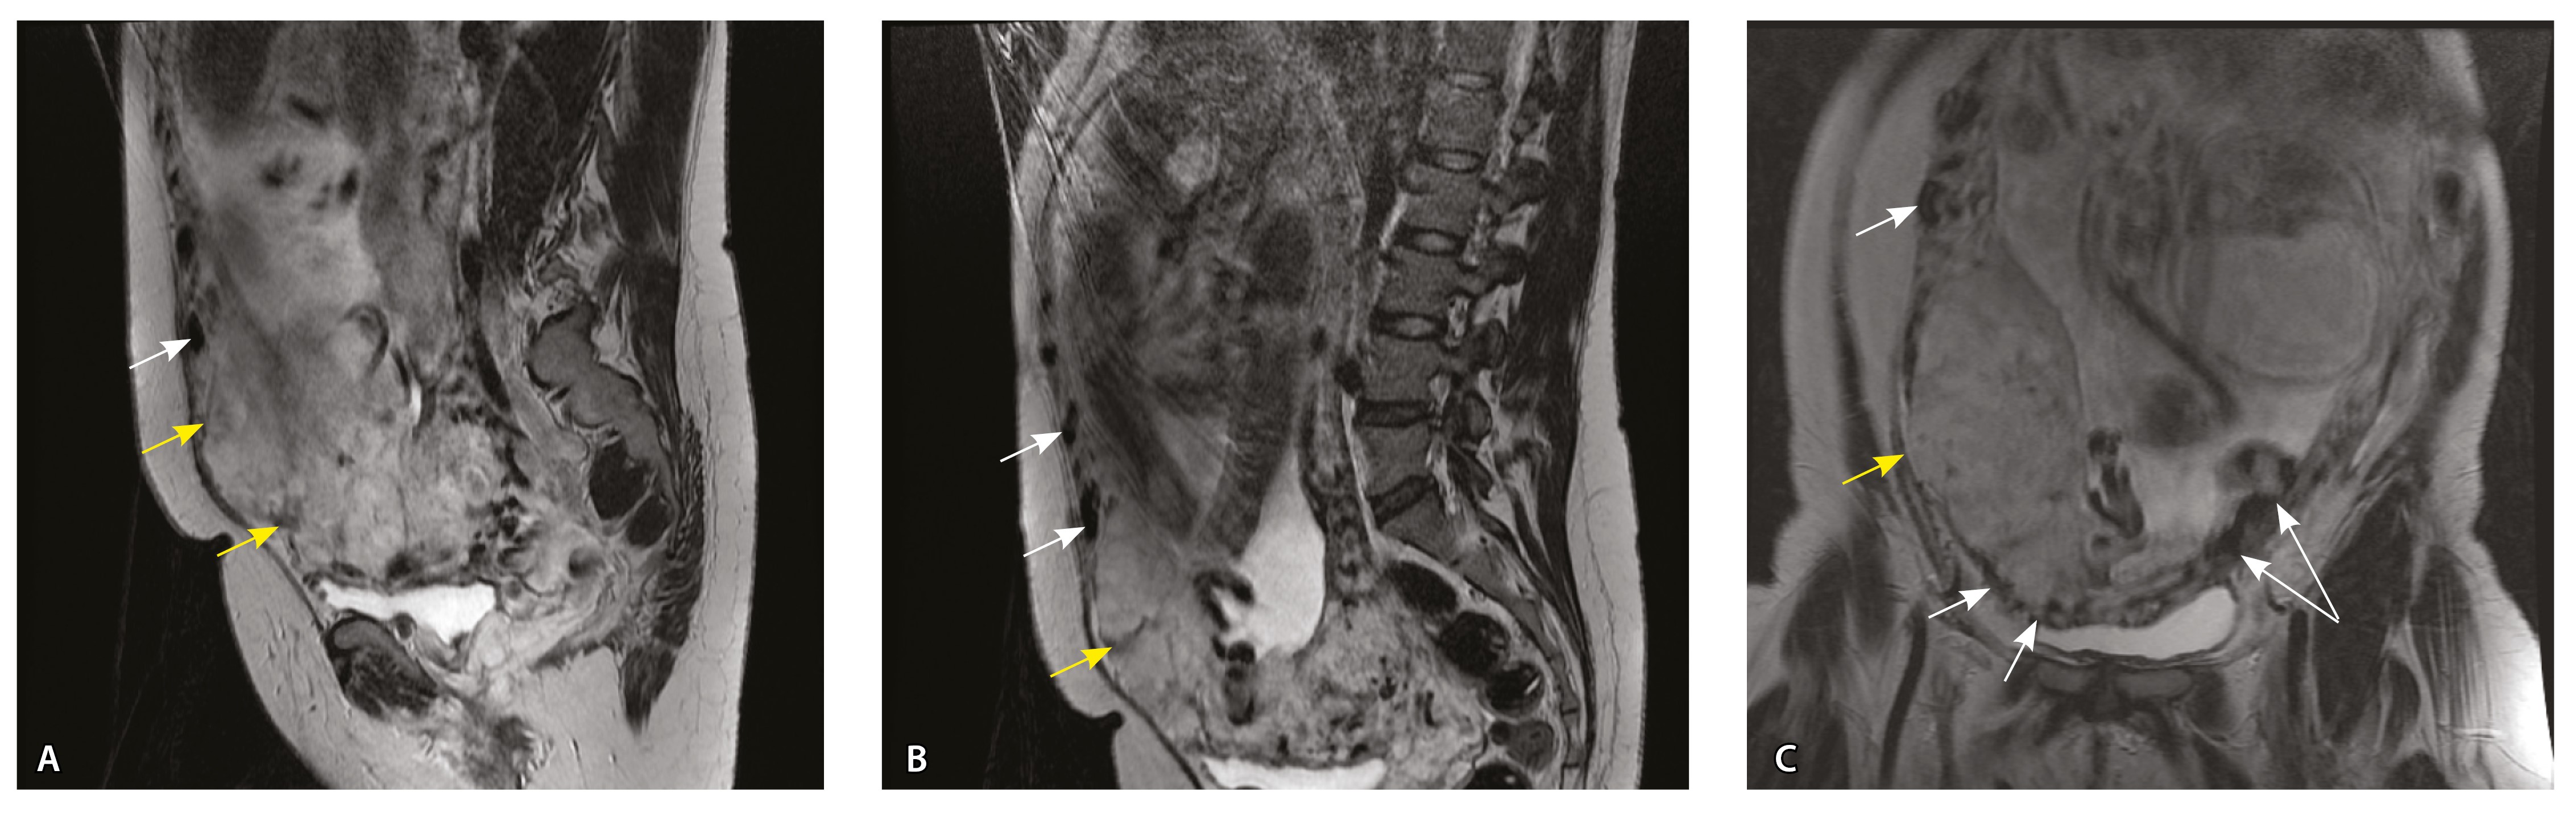

Сосуды 4-го типа. Наличие крупных извитых анастомозирующих сосудов, преимущественно по поверхности матки (в составе серозной оболочки матки) в сочетании с выраженным истончением нижнего сегмента матки (рис. 10).

Рис. 10. Беременность 33 недели, pl. percreta, PAS 3a по FIGO. На магнитно-резонансных томограммах в режиме Т2-взвешенного изображения в сагиттальной (A) и фронтальной (Б, В) плоскостях определяется внутриматочная гиперваскуляризация (желтые стрелки) и гиперваскуляризация в области выраженно истонченного нижнего маточного сегмента, с наличием многочисленных анастомозирующих сосудов по поверхности матки (белые стрелки); стенка матки в данной области представлена ретроплацентарными сосудами

Главным отличием крупных сосудов в составе серозной оболочки является то, что морфологически они находятся в пределах стенки матки. Об этом свидетельствует наличие в операционном материале тонкого поверхностного слоя мезотелия, отделяющего матку от брюшной полости (рис. 11). Его невозможно визуализировать методом МРТ из-за особенностей метода и толщины получаемых срезов.

Рис. 11. Сосуды 4-го типа при гиперваскуляризации стенки матки при патологической инвазии: А – крупный сосуд в составе серозной оболочки матки: справа видны единичные цитотрофобластические клетки (стрелки), не достигающие стенки артерии (иммуногистохимическое исследование, маркер цитокератин 8; × 50); Б – крупные сосуды в составе серозной оболочки: наличие внутреннего слоя эндотелиоцитов (иммуногистохимическое исследование, маркер СD34; × 50)

На микропрепаратах васкуляризация серозной оболочки представлена множеством крупных сосудов, идущих в разных направлениях и анастомозирующих друг с другом. Возможно, имеются артериовенозные соустья. На серийных срезах также видно, что в стенках артерий трудно различимы два слоя миоцитов (продольный и поперечный). Со стороны адвентиции они окружены толстым «футляром» из грубоволокнистой голубой ткани (при окраске по Маллори). Она проникает в стенку артерий, замещая мышечный слой (рис. 12).

Рис. 12. Истончение миометрия; в составе серозной оболочки видна крупная артерия, окруженная плотной соединительной тканью. А – cосуды в составе серозной оболочки (окраска по Маллори; × 200), не дифференцированная на мышечные оболочки стенка артерии, справа – вена, оба сосуда покрыты фиброзной оболочкой, внизу виден слой мезотелия в составе серозной оболочки; Б – серийный срез тех же сосудов при окраске на выявление эластических волокон, сосуд с соединительнотканной муфтой (окраска по Вейгерту; × 50): определяется полная дезорганизация эластичного материала в стенке; стрелкой указан мезотелий (аналог pl. increta, PAS 2 по FIGO)

Эластический каркас представлен сетью тонких волокон, без концентрации на внутреннюю и внешнюю мембраны. Однако маркер СD34 констатирует сохранение эндотелия, что свидетельствует о том, что по артериям циркулирует кровь, не сворачиваясь (рис. 13).

Рис. 13. Самые крупные сосуды в пределах серозной оболочки стенки матки: А, Б – серийные срезы артерии; × 50. При окраске по Маллори (А) видна тонкая полоска мезотелия (черная стрелка), слабо дифференцированная мышечная стенка артерии, вокруг нее – плотная коллагеновая оболочка (желтая стрелка), в просвете определяются тромботические массы. При окраске по Вейгерту (Б) наблюдается полная потеря внутренней и внешней эластических мембран

Анализ частоты встречаемости сосудов 4-го типа при различных степенях приращения плаценты (рис. 14) показал: при плотном прикреплении плаценты (gr 2) и поверхностном приращении (gr 3) сосуды данного типа не выявлены, при pl. increta (gr 4) частота встречаемости незначительная – 16,7%, а при глубокой инвазии плаценты (pl. percreta, gr 5) сосуды этого типа преобладают (р < 0,001, хи-квадрат Пирсона).

Рис. 14. Частота встречаемости сосудов 4-го типа при различной глубине приращения плаценты (grade МАPI-RADS)

Сосуды 5-го типа. Наличие гиперваскуляризации за пределами матки по данным МРТ, на границе с мочевым пузырем с вовлечением его стенки, сосуды в области перешейка матки, параметрия, в том числе в сочетании с признаками фиброза, наличием рубцово-спаечных изменений и др. Можно предположить, что сосуды 5-го типа являются аналогом pl. рercreta PAS 3b, 3c (рис. 15).

Рис. 15. Беременность 34 недели, pl. percreta, PAS 3b по FIGO (A, Б), PAS 3c по FIGO (В). На магнитно-резонансных томограммах в режиме Т2-взвешенного изображения в сагиттальной (A, В) и аксиальной (Б) плоскостях определяется гиперваскуляризация в области выраженно истонченного нижнего маточного сегмента с распространением сосудов на заднюю стенку мочевого пузыря в области дна (белые стрелки), в область перешейка матки (желтые стрелки)